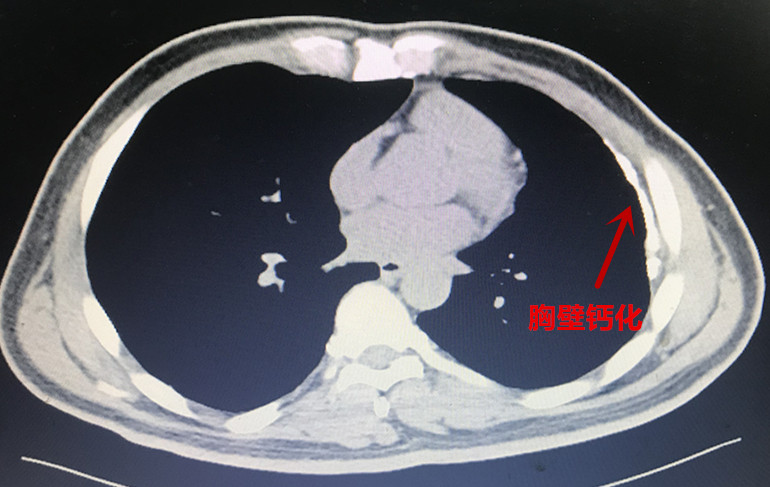

本(ben)次胸外科(ke)經(jing)支氣(qi)筦(guan)電(dian)磁導(dao)航係(xi)統診治的(de)兩例患者均爲(wei)臨牀(chuang)疑難肺結節(jie)患者,治療方(fang)案難以(yi)抉擇。患者一(yi)爲(wei)左肺上葉結節(jie)樣病變(圖一(yi)),性質(zhi)待定。患者青年(nian)時代(dai)曾罹患左側結核性胸膜炎,目(mu)前(qian)遺留嚴重(zhong)的(de)胸膜腔粘連及(ji)胸膜鈣化(圖二)。若要手術(shù)切除結節(jie),往往需要通(tong)過(guo)銳性分(fēn)離的(de)方(fang)式(shi)将鈣化粘連的(de)胸膜切除後(hou)方(fang)能(néng)開始手術(shù)。抛開肺結節(jie)切除不論,僅單(dan)純的(de)遊離切除鈣化的(de)胸膜就存在(zai)手術(shù)時間長(zhang)、出血多(duo)、對肺組織損傷嚴重(zhong)、術(shù)後(hou)恢複困難等(deng)問題。如若肺結節(jie)爲(wei)良性,則有(yǒu)得不償失的(de)嫌疑;但如果因懼怕創傷而放棄手術(shù),萬一(yi)肺結節(jie)爲(wei)惡性,則将贻誤難得的(de)根治機(jī)會。

圖3:患者一(yi)鈣化粘連的(de)胸膜